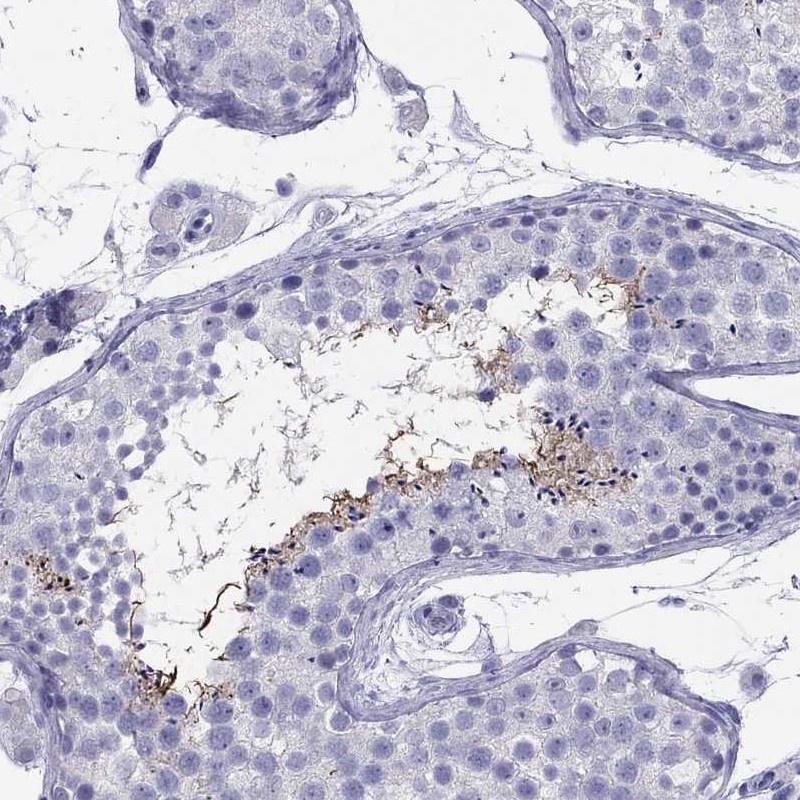

Learn how we validate our antibodies, how we secure their reproducibility, and why we apply enhanced validation. Our antibodies are validated in IHC, ICC-IF, and WB.